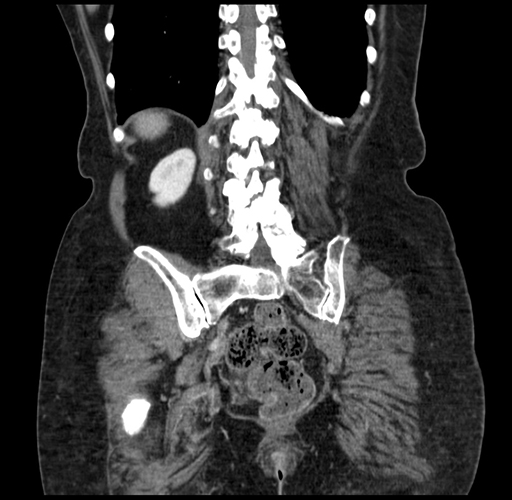

Pre-Chemo: Coronal Venous

Coronal Venous